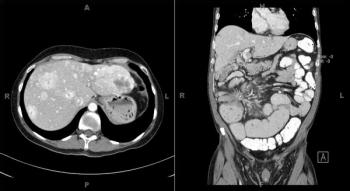

A 56-year-old woman presents with abdominal fullness and virilization. Axial and coronal images from a CT scan of her abdomen are shown below. What is your diagnosis?